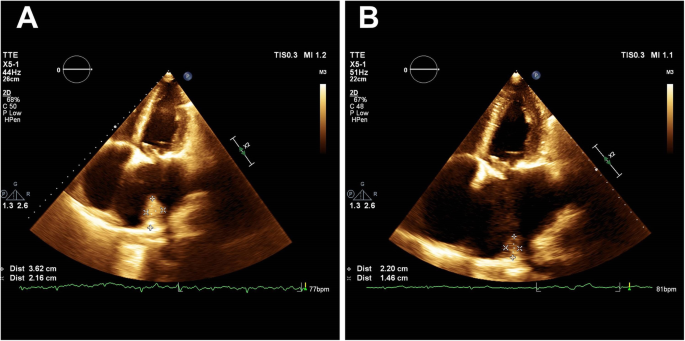

Nine months after the initial cardiac surgery, the combination of clopidogrel and increased anticoagulant therapy (INR 2.89) still had not resolved the thrombus that was verified and quantified by the CMRI. The left atrial size remained approximately the same (93x79mm) and the size of the recurrent thrombus was 90x30mm. The function of mitral bioprosthesis remained normal and the patient was in good clinical condition. A conservative approach was advised as there were no signs of embolic events or cardiac decompensation. The therapy was actually reduced to VKA monotherapy due to patient-referred excessive epistaxis, subcutaneous hematoma formation and pruritus. As long as these bleeding side effects continued to occasionally occur even after the therapy was reduced and laboratory tests furthermore revealed signs of the precipitating hepatopathy, VKA was discontinued after another 6 months from the previous visit (i.e. 15 months after the initial surgery). As all of the guideline-directed therapies had already been applied, combination therapy using rivaroxaban together with clopidogrel was initiated in order to keep effective anticoagulation of the patient and in order to try to dissolve the thrombus. During the last two follow-up visits that occurred after another 3 and 6 months from the last therapy adjustment (i.e. approximately 18 and 21 months after the initial surgery), the patient was still in good clinical condition, without any embolic events and without any signs of clinically relevant bleeding. Subsequent thrombus measurement by echocardiography finally showed a significant gradual decrease in size to 22x36mm and to 14x22mm, respectively (Figure 4A and 4B). The tailored therapy was maintained without any changes and the patient has been invited for a regular check-up in another 12 months.